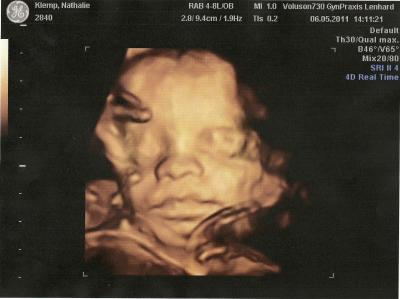

Wollte euch mal meinen süssen vorstellen

Bild zu Wollte euch mal meinen süssen vorstellen - Forum für August - Mamis

wow das ist ja gestochen scharf! Schönes Bildchen!! :-) GLG

Bin richtig stolz auf meinen kleinen Hattest du nicht auch 3D ultraschall am gleichen Tag?? Ich habe am 9.06 nochmal